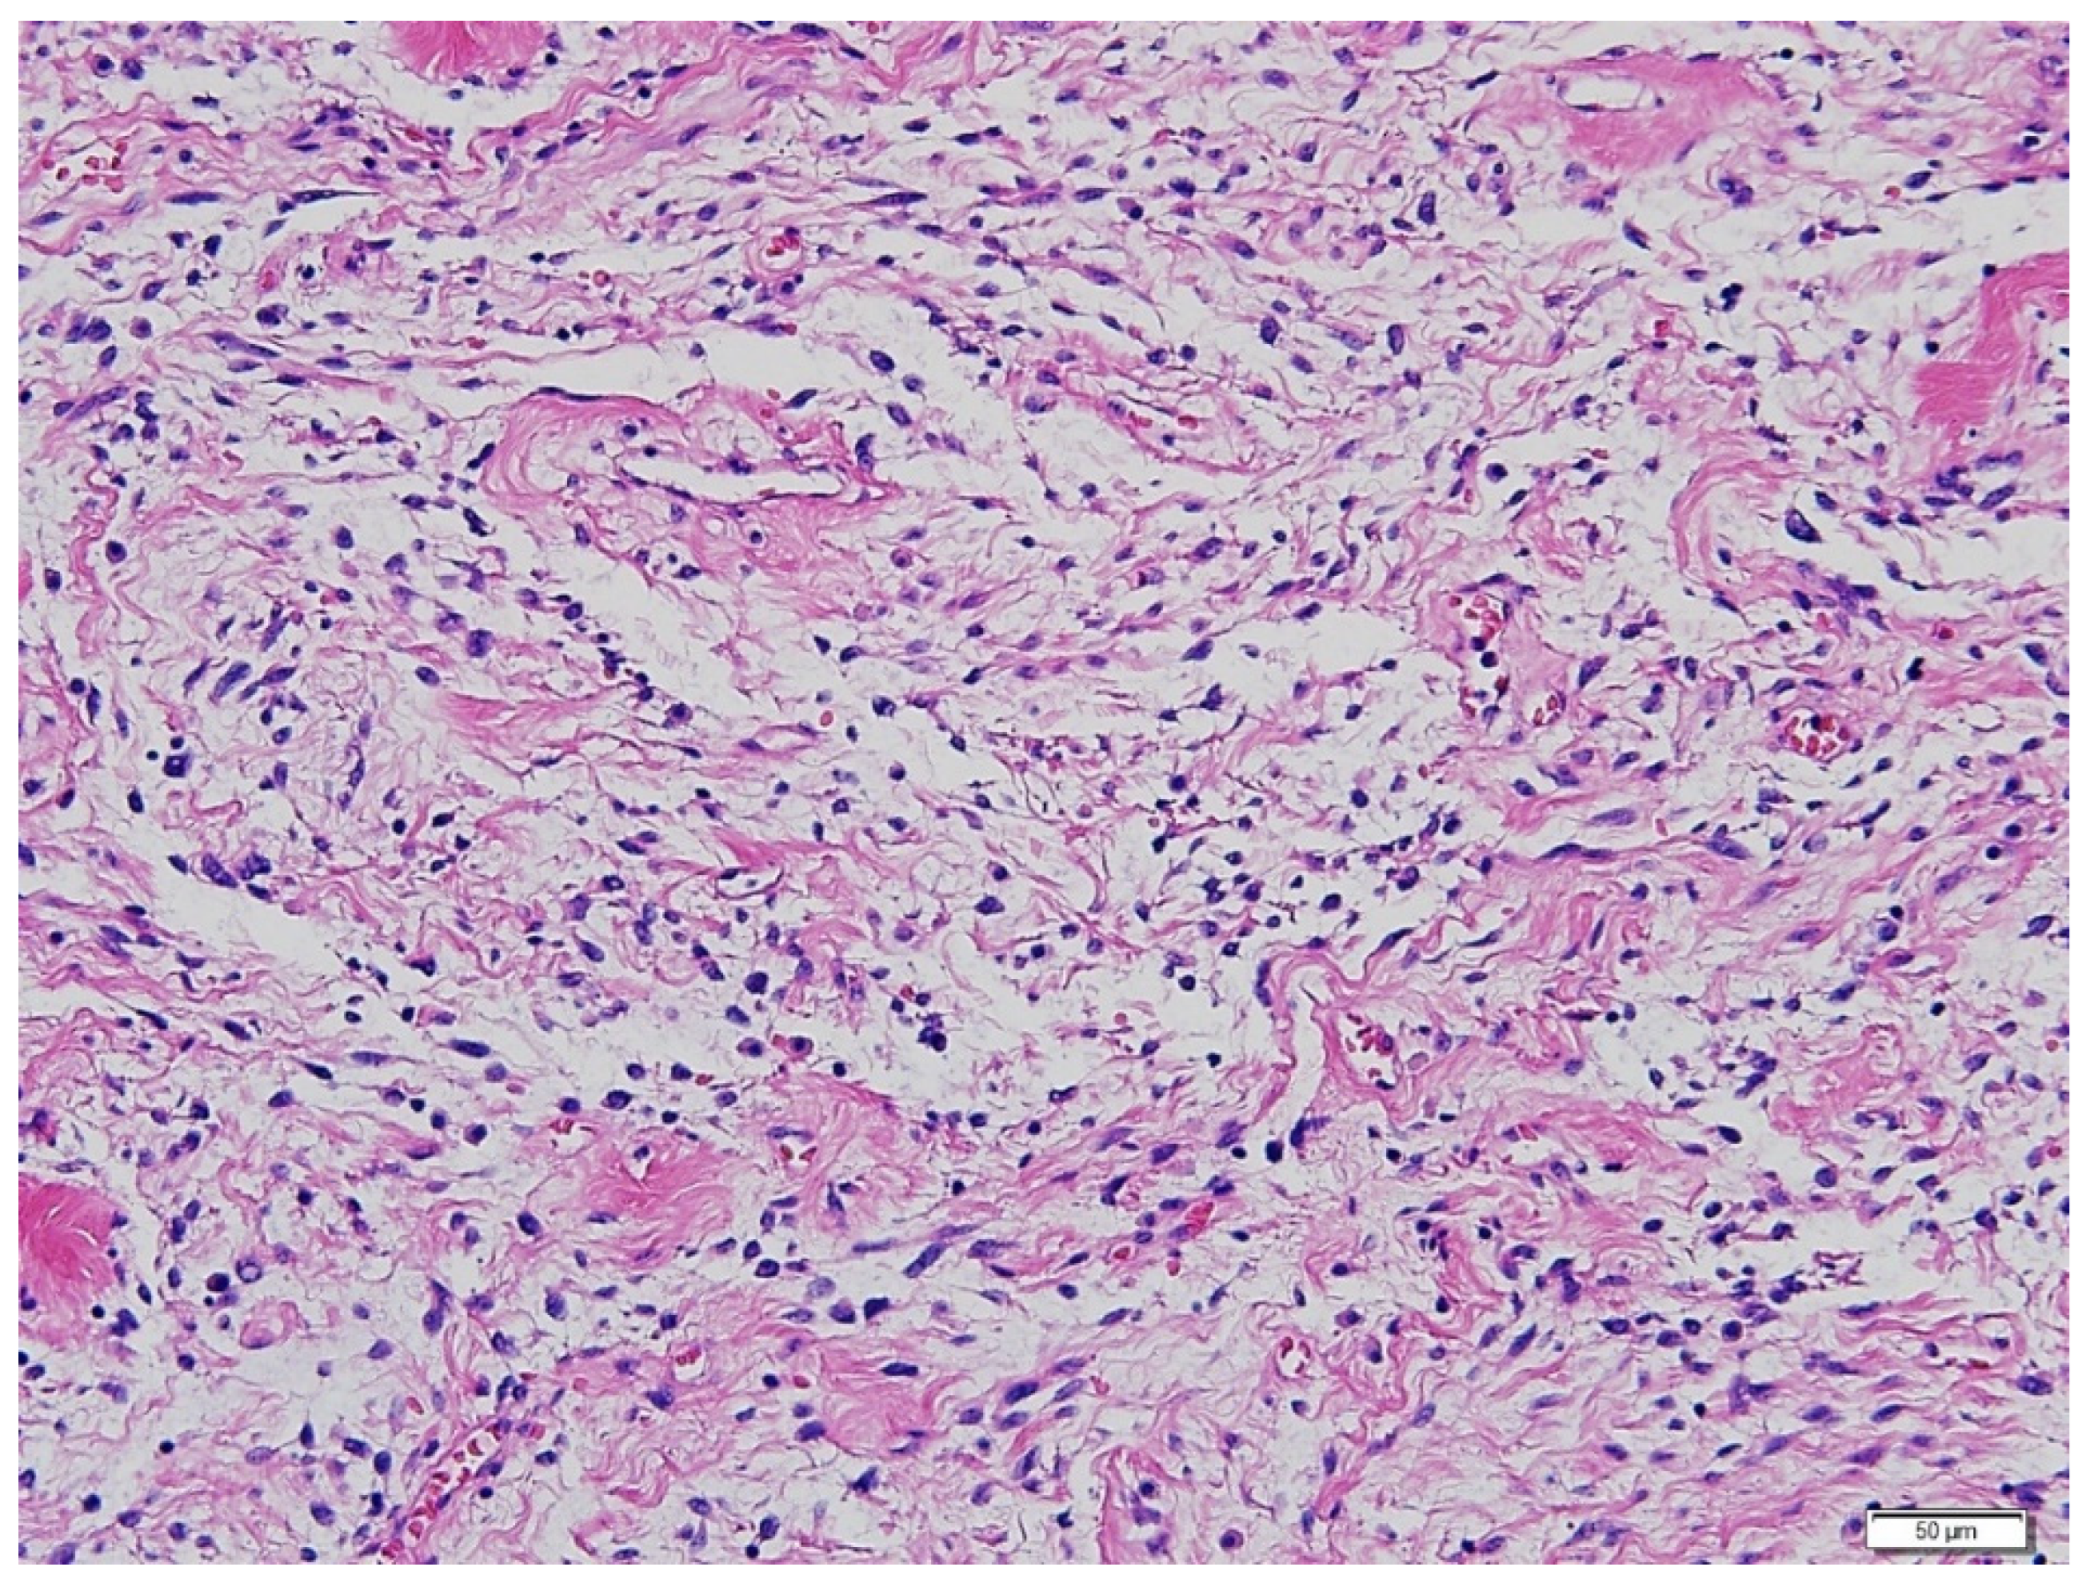

The size and distribution of the pulmonary masses were aggravated along with cystic changes. Considering the rapid growth in a relatively short time and associated distressing symptoms, the decision was made to initiate active antitumor treatment instead of continuing with conservative management and close observation. The patient had previously undergone bilateral salpingo-oophorectomy and was menopausal. Therefore, letrozole, an aromatase inhibitor, was initiated at 2.5 mg once daily. At this time, considering the patient’s aggressive and rapid clinical progression, which was not considered benign, the possibility of malignancy, rather than BML, was raised. Therefore, it was decided to review the surgical specimens of the lung and pelvic masses from 2017. Microscopic examination revealed that the metastatic lung nodules were small, uniform, characterized by bland tumor cells with spindled nuclei and scant cytoplasm, in the background of rich small arterioles or capillary networks (Figure 3). Mitotic counts were up to 1 per high-power field. Necrosis was not present.

Figure 3.

Hematoxylin-eosin staining of the lung mass. Microscopic examination revealed metastatic lung nodules with small, uniform, and bland tumor cells with spindled nuclei and scant cytoplasm, in the background of rich small arterioles or capillary networks. (Magnification 200×).

Immunohistochemical (IHC) staining showed that desmin was expressed in some tumor cells. The tumor cells showed patchy cytoplasmic immunoreactivity with CD10, while additional immunohistochemical staining revealed that caldesmon was diffusely positive in the tumor cells. Diffuse nuclear positivity of tumor cells with Wilms’ tumor-1 (WT-1) was also noted (Figure 4). Based on a thorough review by a gynecologic pathologist, the tissue was found to be more suitably categorized as LG-ESS, rather than BML (Figure 4). Because our hospital does not perform suitable molecular tests for genetic fusions of LG-ESS, such as JAZF1 translocation, molecular alterations could not be evaluated.

Figure 4.

Immunohistochemical staining of the lung mass. (A) Desmin is expressed in some tumor cells (200×), (B) h-Caldesmon is diffusely positive (200×). (C) Tumor cells reveal patchy cytoplasmic immunoreactivity on CD10 (200×). (D) Diffuse nuclear positivity of tumor cells with WT1 (200×).